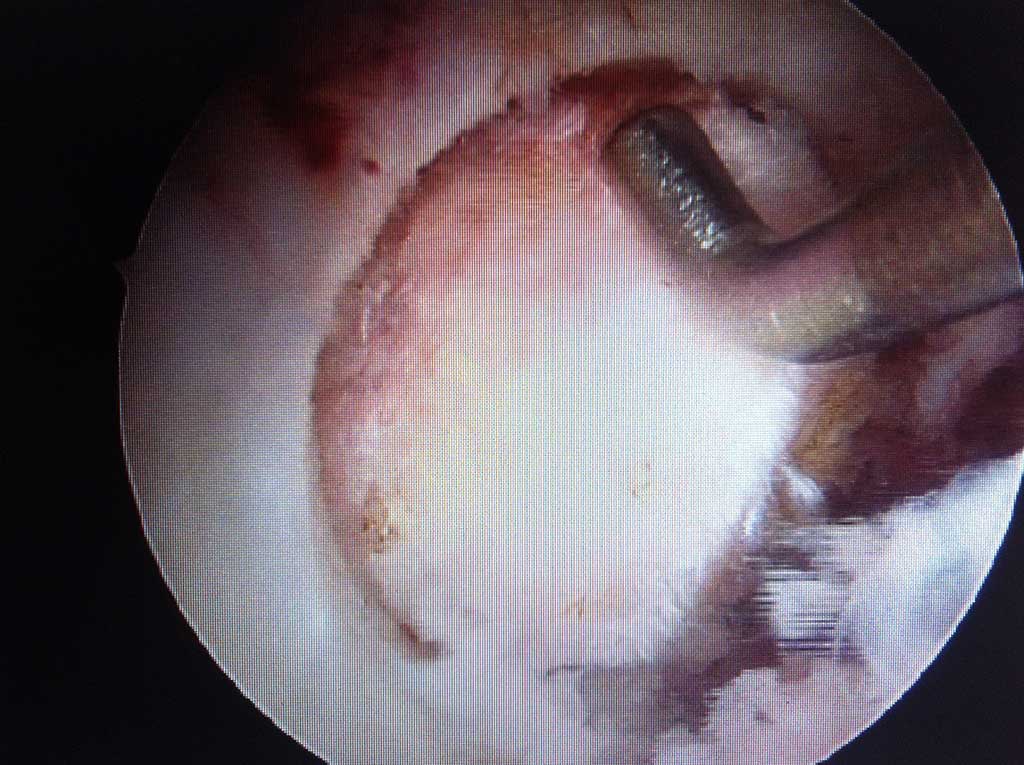

Arthroskopische Meniskus - Teilentfernung

Wie läuft die Operation ab ?

Es handelt sich dabei um einen ambulanten Eingriff in unserer OCD Klinik. Die Operation wird in Spinatanästhesie durchgeführt und dauert einige Minuten. Während des Eingriffes kann dem Patienten, auf Wunsch, auch das operative Vorgehen auf grossem LCD Monitor erklärt werden.

Arthroskopische Microfracturierung

Wie läuft die Operation ab?

Bei gut abgegrenzten Knorpelschaden bis zur 2,5 cm2 Grösse wird im Rahmen einer ambulanten arthroskopischen Operation der frei liegender harter Knochen auf dem Boden des Knorpeldefektes an mehreren Stellen perforiert ( " eingebrochen " = fracture ). Aus diesen Öffnungen kommt es zur Einblutung des Knorpeldefektes und aus dem Blutgerinsel ( Koagel ) entsteht innerhalb von 6-10 Wochen ein Knorpelregenerat ( "Knorpelnarbe") Die OP Dauer beträgt in Spinalanästhesie 15-30 Minuten.